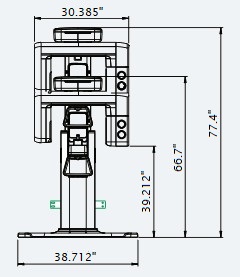

| Without CEPH unit | With CEPH unit | |

| FRONT VIEW |

|

|